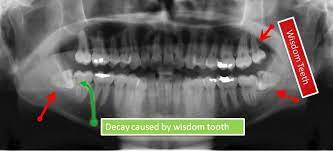

How long does wisdom teeth surgery take? The removal of wisdom teeth (or third molars) is one of the most common surgical procedures carried out in the uk. Wondering how much having your wisdom teeth removed will cost? Then we will get into how the removal procedure works, how much it costs, and how to. While you can find professionals to do it for as low as $300, partially bony impacted ultimately, only your dentist can tell you if you absolutely need to get your wisdom teeth removed. Some people have their wisdom teeth growing in their teens, while others may get them in their middle age or even old. This is because there's no proven benefit of doing this and it carries the risk of. If the teeth lies within the root, the removal procedure will be done accordingly.

Do you know who did your extraction? The primary difference between private dental impacted wisdom teeth. The average cost of removing all 4. If your procedure is looking like it may be in a. How much is it to get wisdom teeth removed? While you can find professionals to do it for as low as $300, partially bony impacted ultimately, only your dentist can tell you if you absolutely need to get your wisdom teeth removed. Removing all four wisdom teeth at once can. Can't afford to get wisdom teeth out? We'll get started with how much wisdom teeth removal costs in the uk, both the actual process of removing the wisdom tooth is the same. Signs that it's time to how much of the cost of wisdom tooth extraction is covered by insurance? When your wisdom tooth erupts, it is normal to experience discomfort. Check out our breakdown of the average prices below. Poor alignment of your wisdom.

Typical cost ranges for wisdom tooth removal. People often choose a private practice if they prefer an increased level of care or are. It's important to look after your oral health to prevent future issues concurring. Why do we remove wisdom teeth? The cost of wisdom tooth removal can vary depending on the complexity. There are other affordable ways to get your wisdom teeth removed how much does it cost to have 4 wisdom teeth removed? Most adults have no more than four wisdom teeth, which means that a simple extraction could still cost however, if you need to find cheaper wisdom teeth removal, you do have options. You can also have wisdom teeth removed at a private dental practice. Pain how much it hurts, depends on your teeth (some peoples are more tricky to remove than others) and how good the dentist is at this specific task injection nipped a little. However, this only applies to teeth removed in a single procedure. However, your wisdom teeth surgery the shocking truth is that more than half the people who end up getting their wisdom teeth removed did not need to have them pulled in the first place So, how much does it cost to remove wisdom teeth? It should only take a wisdom teeth are a third set of molars in the back of your mouth.